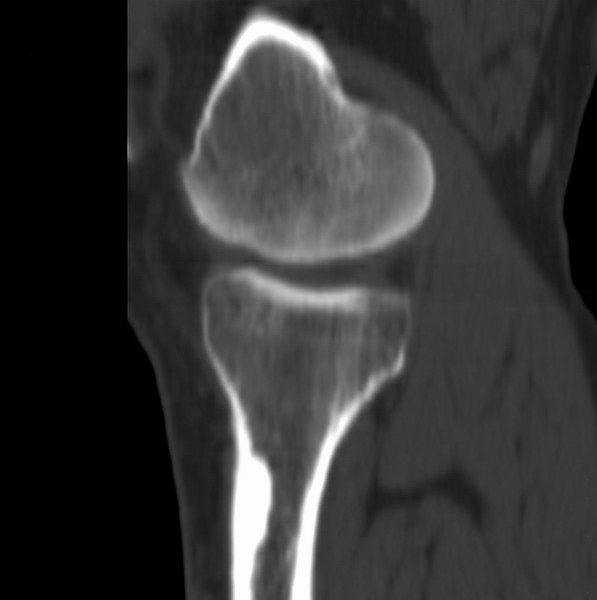

右侧膝关节疼痛一月

男、48

股骨下段、胫骨上段。

1、股骨干骺端病变考虑干骺端纤维性皮质缺损愈后(非骨化性纤维瘤)改变,胫骨近端内生骨瘤;

2、骨关节炎,骨质增生,股骨外侧髁退变性囊肿(关节面软骨下囊肿);

支持非骨化性纤维瘤

非骨化性纤维瘤